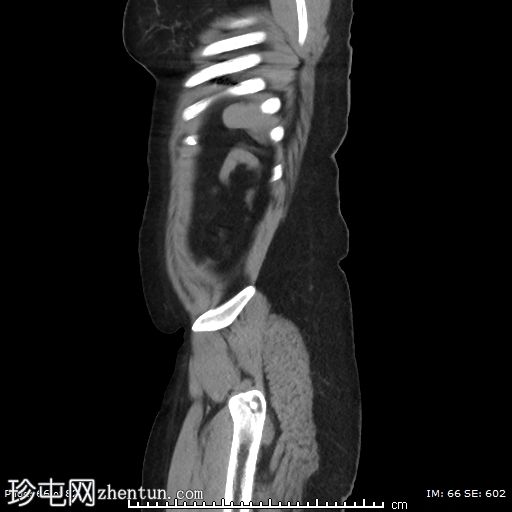

矢状位平扫

左侧附件血管蒂扭转,形成血管和软组织呈漩涡状排列,高度提示卵巢扭转。

可见轻度卵巢周围脂肪条索状改变和少量邻近盆腔积液,可能为继发性充血和水肿。

由于左侧附件增大的组织结构压迫,子宫向右侧移位。